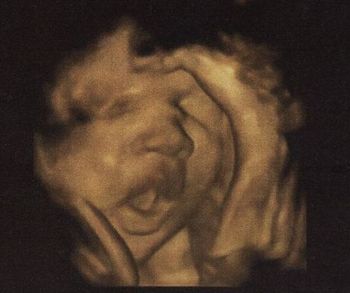

Ja és a fej 2mm-t nőtt, a combcsont 1-et (mármint a múlt heti kórházi adatokhoz képest), ami dicséretes, de így is le van maradva 3 héttel. Megint jött a kórházba befekvéssel, én meg közöltem, hogy még mindig nem kérek belőle.

Totál elegem van, jó lenne már túllenni az egészen. Ja és a flowmertria, nst jó lett, nem lehet semmibe belekötni azon kívül, hogy kicsi a gyerek feje, de könyörgöm azzal meg mit lehet tenni??